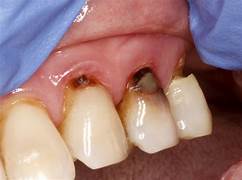

5. Caries radiculares

Las caries en la raíz del diente suelen aparecer debido a un cúmulo de circunstancias que suceden durante la menopausia.

En primer lugar, contribuye a esto la gingivitis descamativa, porque deja la raíz del diente expuesta a agentes externos.

En segundo lugar, la caries encuentra en la sequedad bucal un ambiente propicio para desarrollarse.